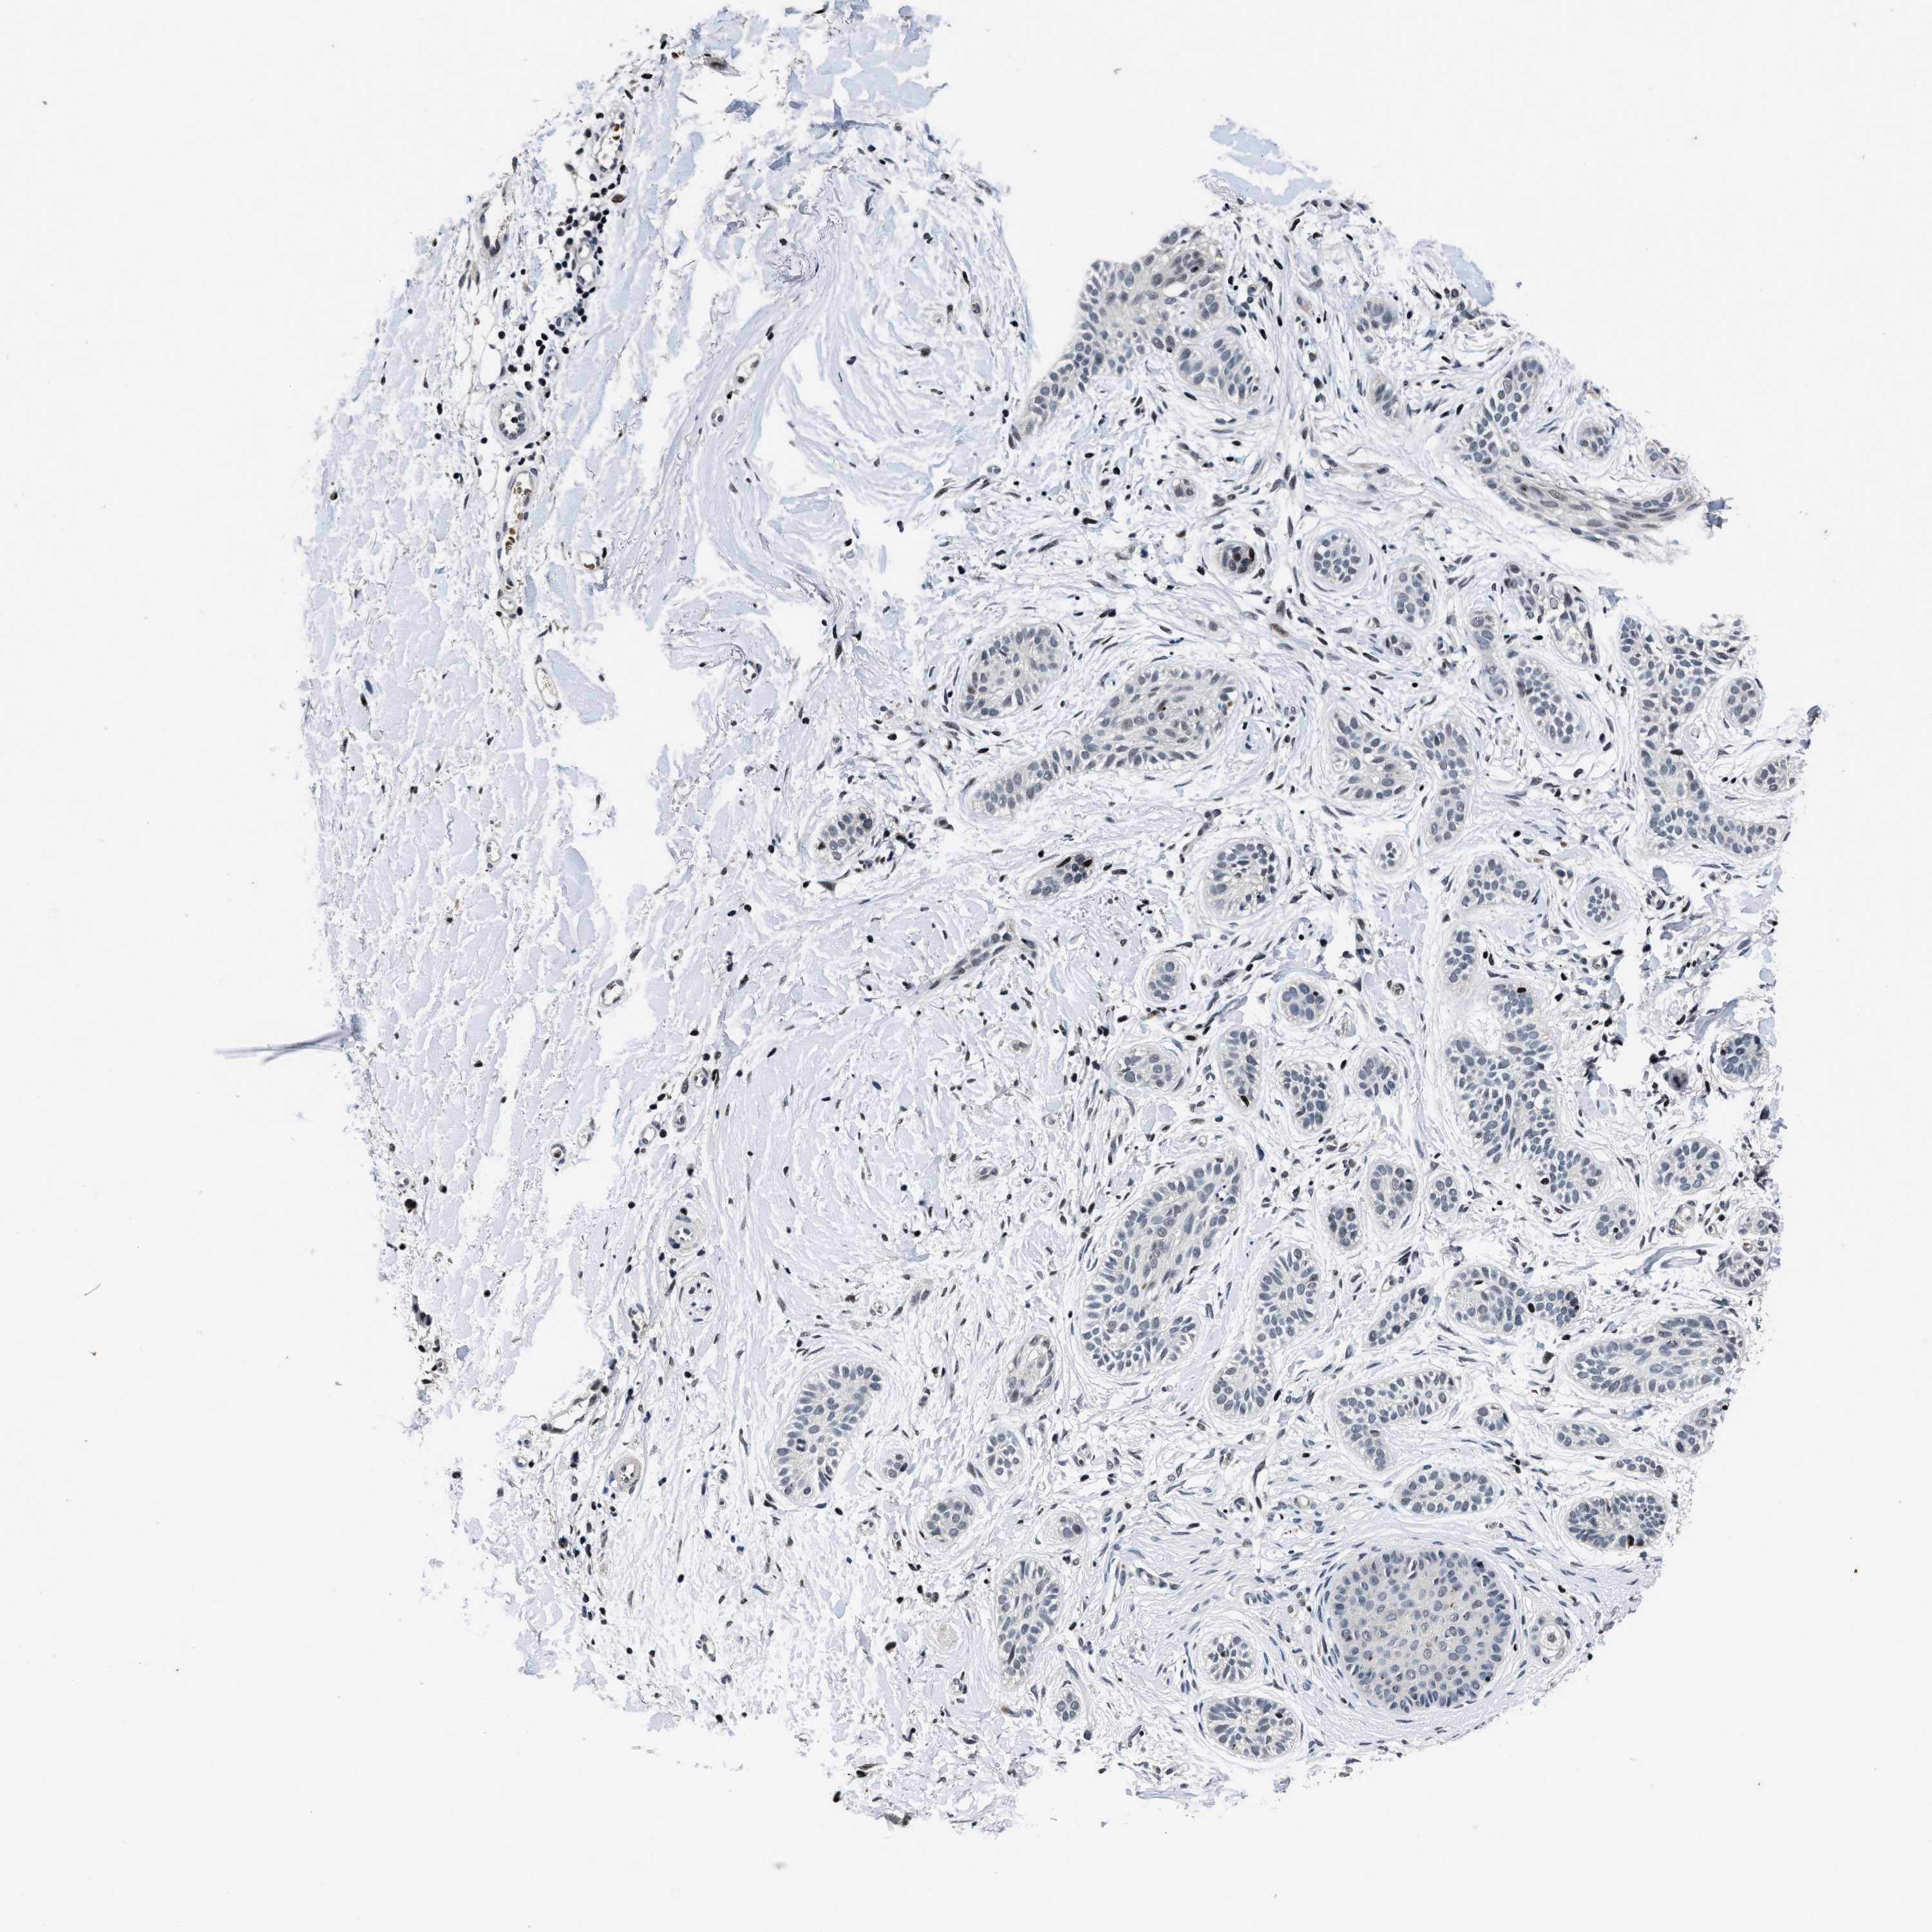

SKIN CANCER - Protein expressioni

A mouse-over function shows sample information and annotation data. Click on an image to view it in a full screen mode. Samples can be filtered based on level of antibody staining by selecting one or several of the following categories: high, medium, low and not detected. The assay and annotation is described here.

Antibody staining in the annotated cell types in the current human tissue is reported as not detected, low, medium, or high, based on conventional immunohistochemistry profiling in selected tissues. This score is based on the combination of the staining intensity and fraction of stained cells.

Each image is clickable and will lead to virtual microscopy that enables deeper exploration of all samples and also displays staining intensity scores, fraction scores and subcellular localization as well as patient and tissue information for each sample.

Antibody HPA020975

Basal cell carcinoma